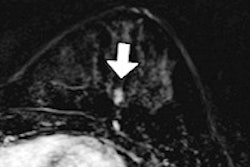

MRI of a 47-year-old woman with invasive ductal carcinoma. Initial axial contrast-enhanced MR images without CAD (above) and with CAD (below) show enhancing mass in left posterior lateral breast that is more evident with CAD color overlay. Images courtesy of AJR.